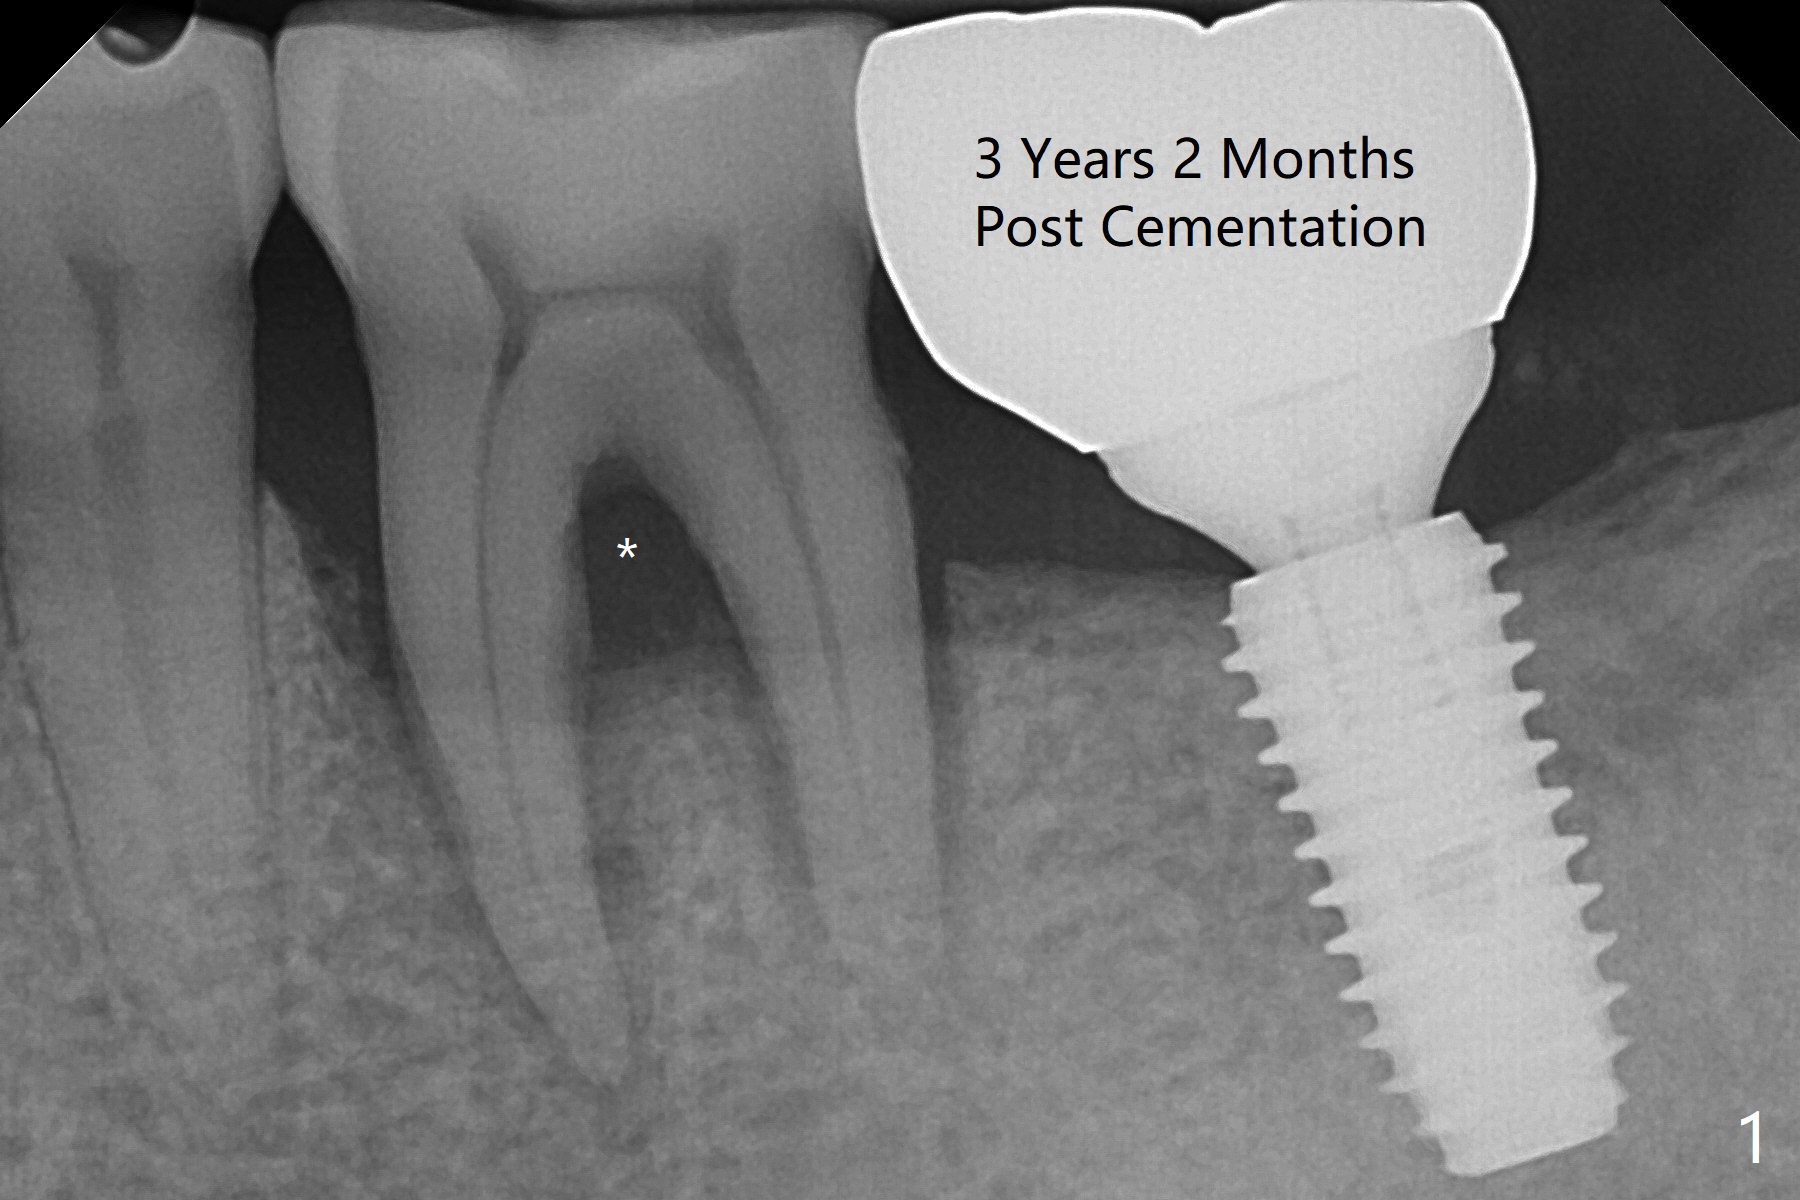

A 58-year-old man requests extraction of the tooth #19 with supraocclusion (Fig.1). After extraction, the septal gingiva has to be sectioned to remove underlying granulation tissue thoroughly. The buccal plate is missing. Ossogen (allograft, Fig.2 *) is placed around the septum (red dashed line). The socket opening is covered by BioXclude and approximated with 4-0 PGA suture, followed by periodontal dressing. With the septum's support, bone graft is expected to heal without too much ridge collapse. The mesial and distal sockets behave as 2 small premolar ones, getting ample blood supply. The socket heals in 20 days (Fig.3). The sockets heal with preservation of the septum (Fig.4: S), while there is formation of the cortical plate on the top of the ridge 10 months postop (Fig.5: ^). It is safe to place a 5x10 mm implant with guide (Fig.6), whereas it may be necessary to place bone graft lingual to the implant at #18 associated with free hand surgery (Fig.7: >). Return to Lower Molar Immediate Implant, No Deviation 18 种植 位点保存 Xin Wei, DDS, PhD, MS 1st edition 01/22/2020, last revision 07/03/2021